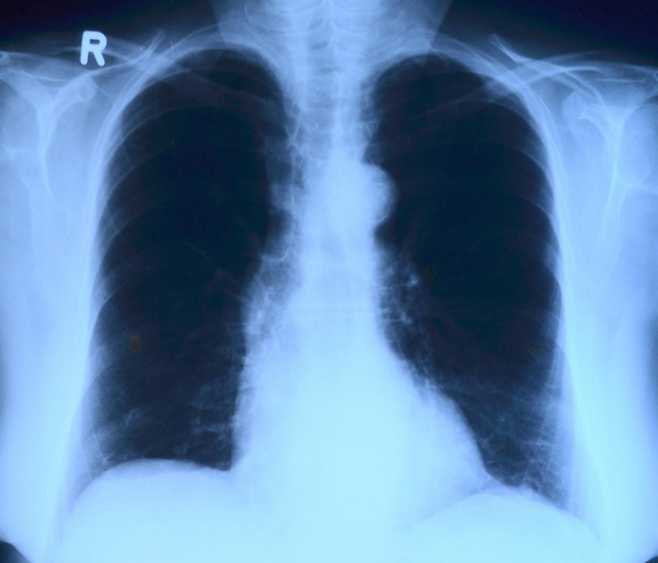

폐는 더 솔직합니다

폐는 회복력이 강한 장기지만, 담배 연기에 노출되는 순간 염증 반응이 즉각적으로 시작됩니다.

기침이나 가래가 없어도, 숨이 차지 않아도 미세한 손상은 이미 누적되고 있을 수 있습니다. 문제는 이런 변화가 상당히 진행될 때까지 증상이 거의 없다는 점입니다.